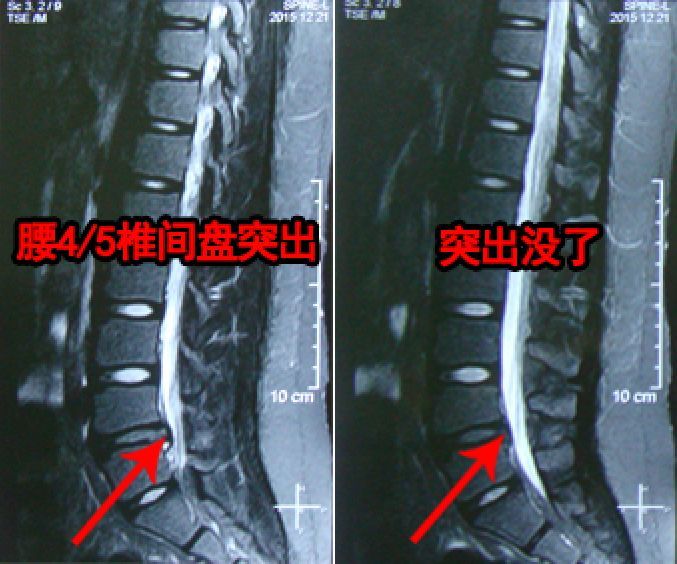

被诊断为轻度腰突

使用腰间盘膏1周左右

腰疼症状明显缓解了

还可以做些轻微的运动

继续使用了1个月时间

腰椎完全康复了